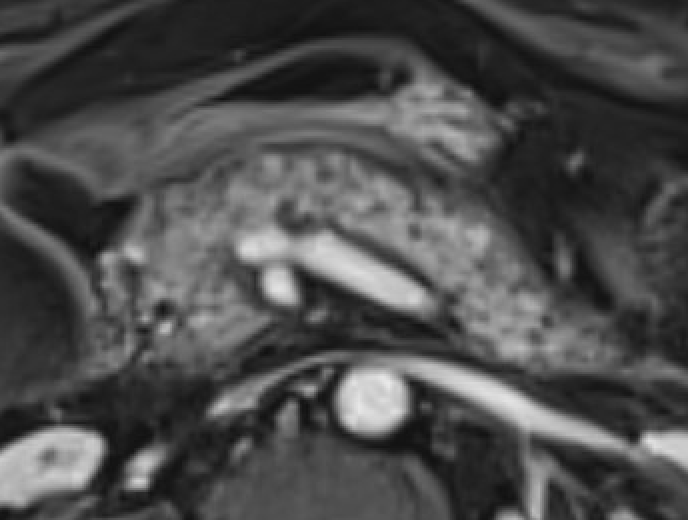

Pancreatic trauma Full-thickness laceration = T2-hyperintense linear signal disrupting parenchyma. Trace pancreatic duct on T2W axial images (MRCP often limited by surrounding fluid) Ductal injury (AAST Grade III+) = surgical indication. MRI better than CT for delineating duct integrity. Contusions (Grade I/II) without duct injury → conservative